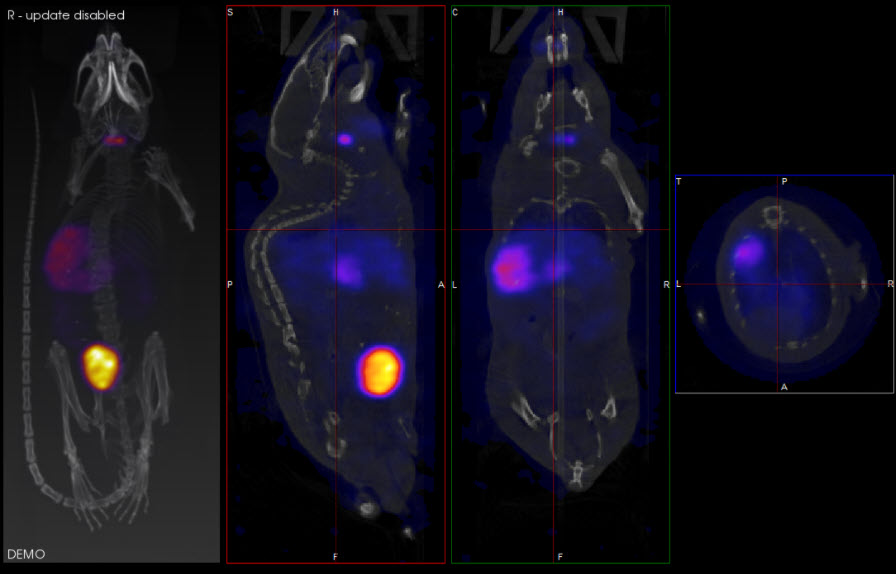

The Slice View (default) simultaneously displays images of single slices for the sagittal, coronal, and transversal views of the loaded data sets.

Slice View Display

In the example image below, the transversal view is the active view. The ← and → keys move the crosshairs towards the L (left side) and R (right side) in the transversal slice, respectively. Moving through the object to the left or right steps through the sagittal plane of the object; thus, the sagittal slice changes.

The ↑ and ↓ keys will move the crosshair towards P (posterior side) and A (anterior side). Both these sides are also visible in the sagittal slice of the object (rotated 90-degrees). Using the ↑,↓ keys in the transversal plane will shift the vertical crosshair in the sagittal plane, and step through the coronal views of the object.